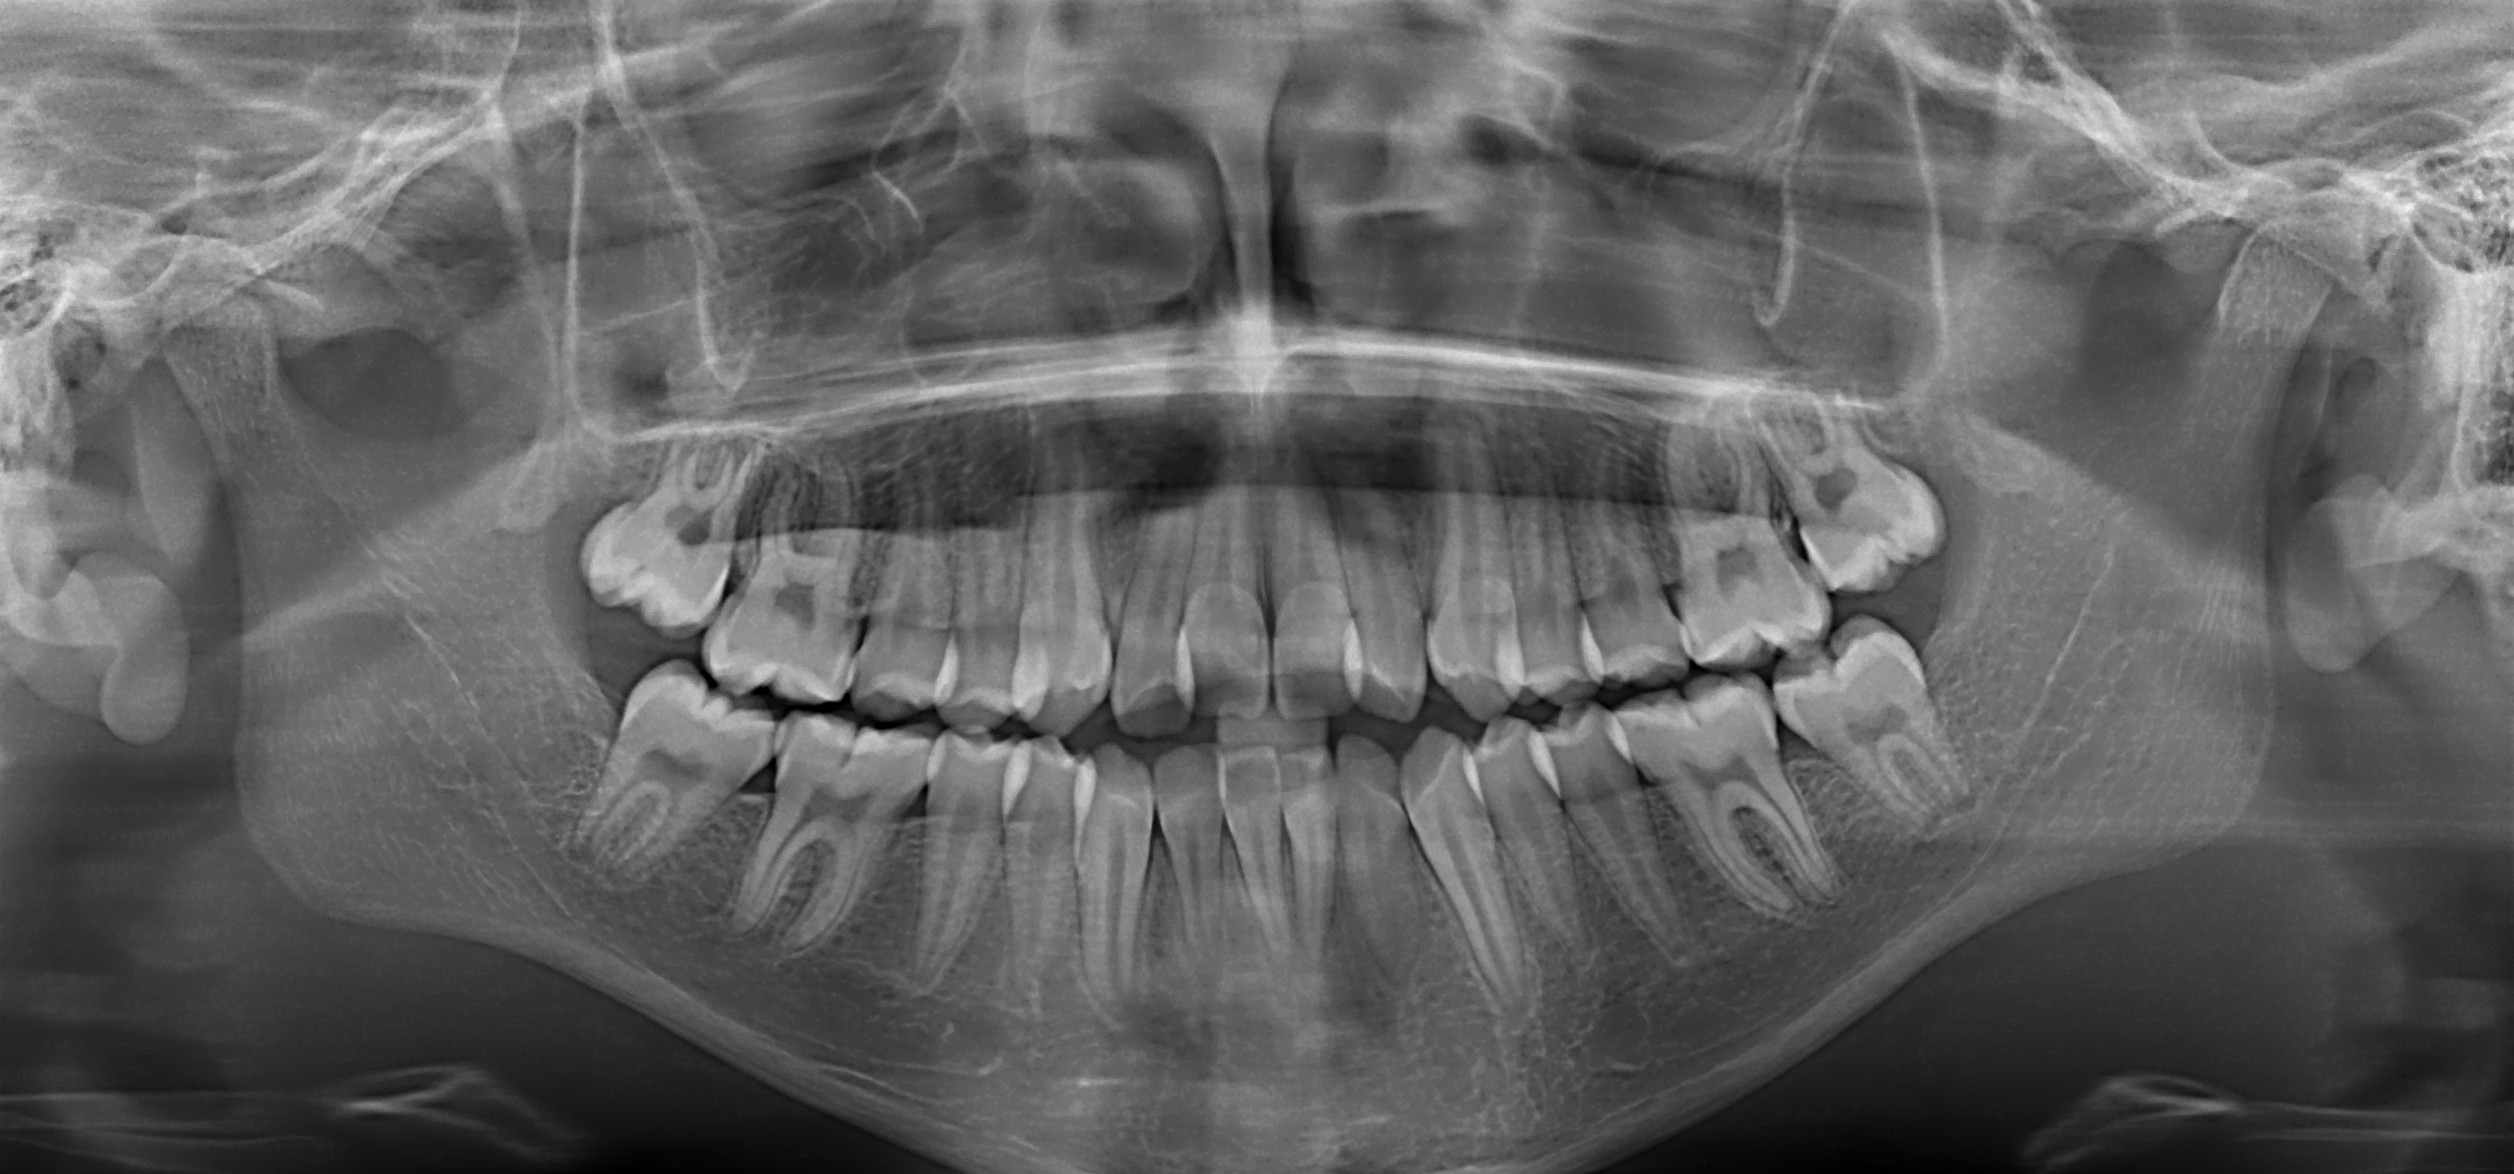

Radiografía Panorámica Digital

En Sinna contamos con tecnología digital de alta precisión para realizar tu radiografía panorámica, un estudio fundamental para obtener una visión completa de tu salud bucal en una sola imagen.

La radiografía panorámica permite evaluar dientes, raíces, hueso maxilar, mandíbula y articulaciones, facilitando un diagnóstico rápido, seguro y confiable para planificar tu tratamiento.

¿Qué nos permite evaluar?

- Estado general de todos los dientes (erupcionados y retenidos).

Presencia de caries profundas o infecciones.

Evaluación para ortodoncia.

Planificación de implantes dentales.

Quistes, lesiones óseas o alteraciones.

Terceras molares (muelas del juicio).